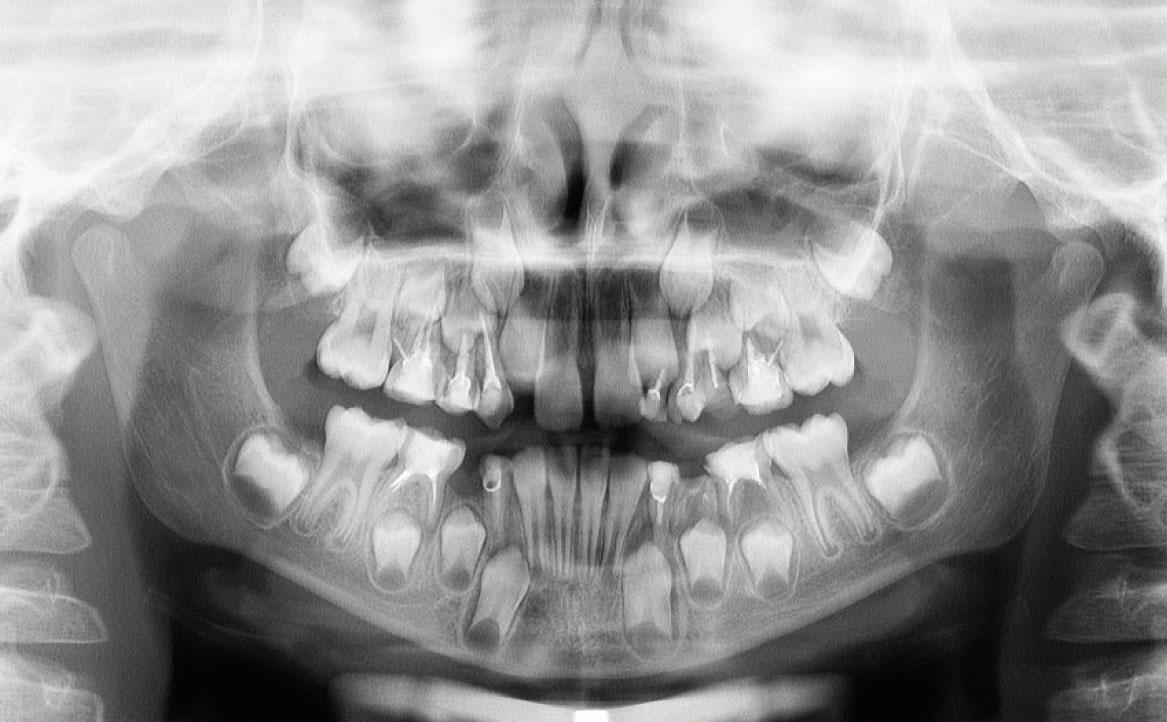

Tale affermazione è stata dimostrata dall’analisi dell’ortopantomografia, in cui era evidente la presenza di materiale non riassorbile, presumibilmente materiale di otturazioni canalari per elementi definitivi, utilizzato in questo caso clinico in elementi dentali decidui, con conseguente difficoltà nel processo di esfoliazione e riassorbimento delle radici stesse (fig. 1).